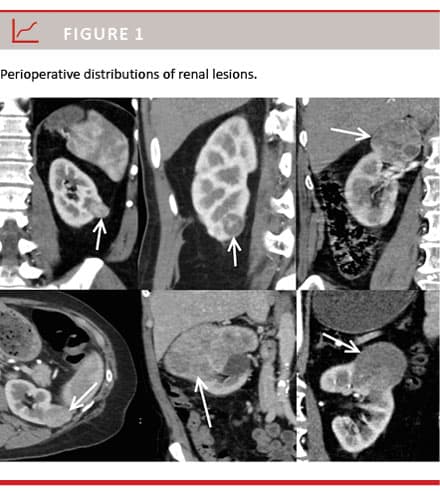

A total of 226 patients underwent PN or RN, and 75 patients were excluded from the study: 25 patients with cystic lesions, 16 patients who had undergone kidney biopsy prior to surgery, 14 patients who had locally advanced lesions and 20 patients with metastatic disease. A total of 151 patients were included in the study. In these patients, CT revealed suspected renal lesions and patients underwent RN or PN. The distribution of lesions is shown in Figure 1. The mean age was 62.9 years (range: 37-86 years) with a male:female ratio of 3:1. The median tumour size was 4.2 cm (range: 1.1-22 cm). The median SL size was 2.5 cm (range: 1.1-4.0 cm), median IL size was 5.5 cm (range: 4.2-7.0 cm) and the median LL size was 11.0 (range: 7.5-22 cm). PN was performed in 69.3% of SL patients versus 23.4% of IL patients (p < 0.001). All LL patients underwent RN. The distribution of benign lesions was not significant in all cohorts (p = 0.27).